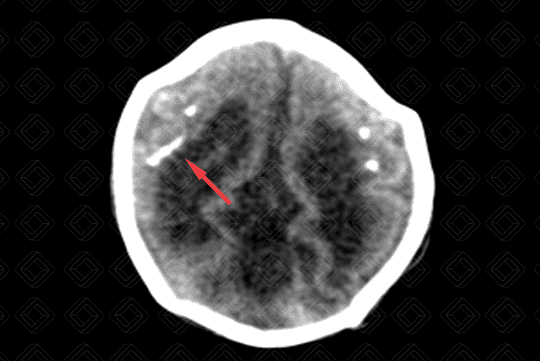

• Tomografia computadorizada do crânio evidenciando microcefalia, com importante atrofia cortical e dilatação compensatória do sistema ventricular;

• Observa-se a presença de calcificações de distribuição corticossubcortical (setas vermelhas) no parênquima encefálico e algumas menos evidentes, nos núcleos da base;